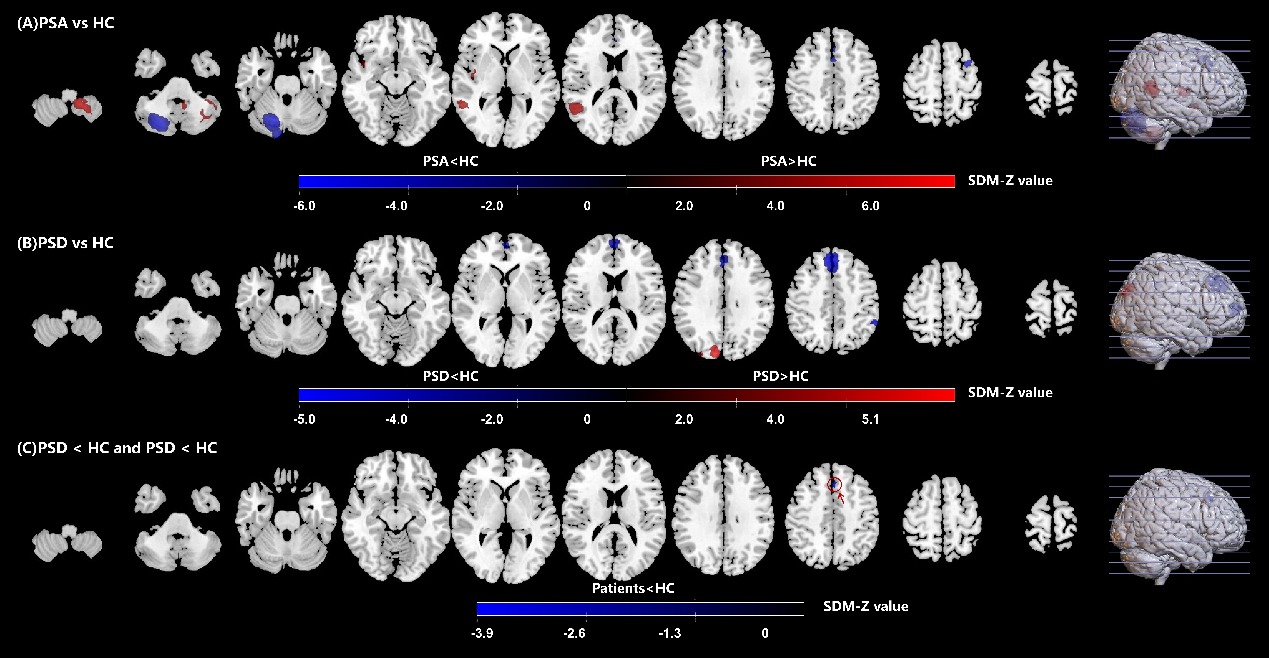

结果 PSA共纳入17篇文献,涉及患者339例,对照组351例;PSD共纳入5篇文献,涉及患者102例,对照组149例。PSA左侧小脑9区、右侧颞中回、右侧脑岛的自发神经功能活动高于对照组 (P < 0.05),右侧小脑6区、左侧内侧额上回、左侧额中回、右侧前扣带与旁扣带脑回自发神经功能活动低于对照组(P < 0.05);PSD患者右侧楔叶、右侧枕上回的自发神经功能活动高于对照组(P < 0.05),左侧内侧额上回、左侧顶下小叶的自发神经功能活动低于对照组 (P < 0.05)。PSA和PSD在左侧内侧额上回的自发神经功能活动均低于对照组 (P < 0.05)。

结论 PSA的病理学机制可能涉及语言功能网络右侧代偿性亢进与左侧功能抑制,并伴有小脑的交叉性协同活动;PSD的发生可能与右侧枕叶网络功能亢进与左侧额顶叶网络功能抑制有关;左侧内侧额上回(MNI坐标x = 0, y = 26, z = 44)功能抑制很可能是PSA与PSD的语言-情绪整合通路,介导PSA与PSD共病的发生。

PSA与PSD的自发神经功能活动差异区域"

| MNI坐标(x, y, z) | AAL脑区(Brodmann分区) | 团块大小/voxels | SDM-Z值 | P值 | I2/% |

|---|---|---|---|---|---|

| PSA > 对照组 | |||||

| -18, -50, -48 | 左侧小脑9区(NA) | 1050 | 5.978 | 0.001 | 1.042 |

| 56, -50, 4 | 右侧颞中回(BA21) | 435 | 4.592 | 0.001 | 18.489 |

| 42, -10, 6 | 右侧脑岛(BA48) | 101 | 4.535 | 0.008 | 0.972 |

| 42, 6, -14 | 右侧脑岛(BA48) | 19 | 4.414 | 0.032 | 0.858 |

| PSA < 对照组 | |||||

| 18, -68, -28 | 右侧小脑6区(BA19) | 1822 | -6.002 | 0.001 | 1.554 |

| 2, 24, 40 | 左侧内侧额上回(BA32) | 242 | -4.793 | 0.006 | 5.643 |

| -34, 8, 60 | 左侧额中回(BA8) | 45 | -5.064 | 0.014 | 11.292 |

| 6, 32, 22 | 右侧前扣带与旁扣带脑回(BA32) | 40 | -4.234 | 0.030 | 1.224 |

| PSD > 对照组 | |||||

| 10, -86, 32 | 右侧楔叶(BA19) | 265 | 5.014 | 0.001 | 0.209 |

| 30, -88, 30 | 右侧枕上回(NA) | 13 | 4.051 | 0.038 | 9.236 |

| PSD < 对照组 | |||||

| 2, 38, 42 | 左侧内侧额上回(BA9) | 954 | -5.104 | 0.001 | 4.256 |

| -2, 60, 10 | 左侧内侧额上回(BA10) | 299 | -4.514 | 0.001 | 1.419 |

| -56, -44, 42 | 左侧顶下小叶(BA40) | 119 | -4.428 | 0.005 | 3.653 |

| PSA < 对照组且PSD < 对照组 | |||||

| 0, 26, 44 | 左侧内侧额上回(BA8) | 65 | -3.883 | 0.008 | 48.200 |